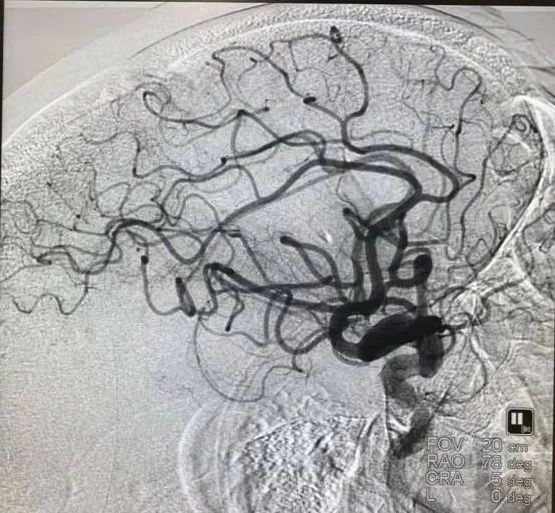

患者发病到入院时间超过4.5h时间,静脉溶栓时间窗超过,考虑大血管病变,患者急诊CT提示左侧大脑中动脉高密度征,ASPECTS评分9分,未见明显低密度灶,结合患者急诊查体,高度提示左侧颈内动脉系统大动脉闭塞。与家属沟通后,急诊行DSA,必要时予血管内治疗。

急诊头颅CT:左侧大脑中动脉高密度征,

ASPECT评分:9分。

术后造影,mTICI分级III。